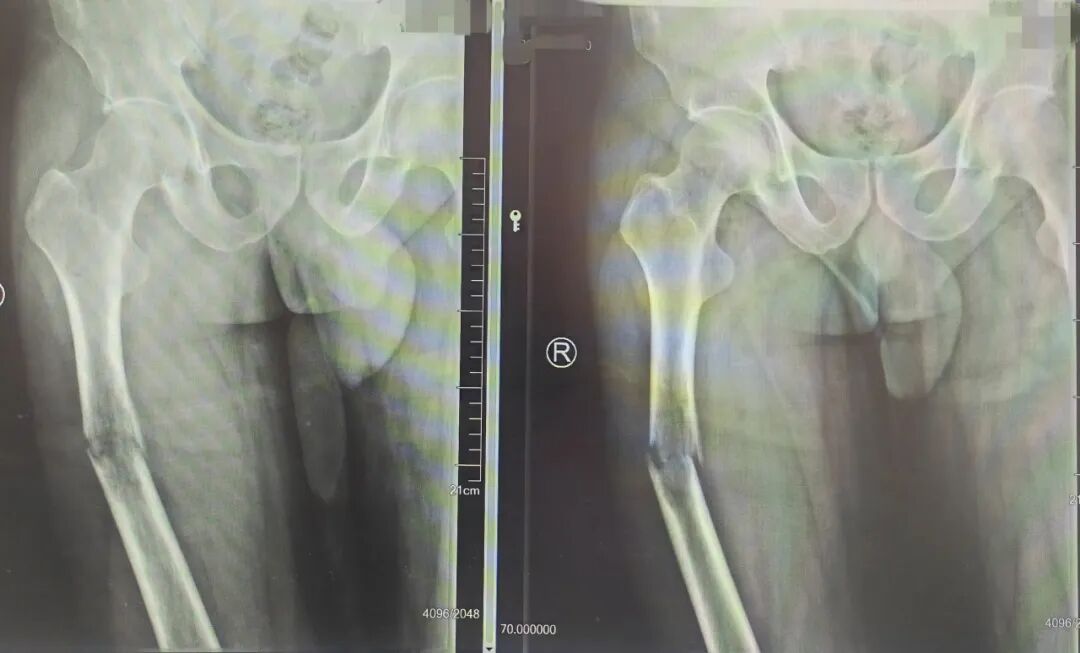

50岁的董先生因右腿骨折入院,经周长明主任仔细问询与全面检查后,得知该患者系恶性肿瘤晚期,还伴随免疫缺陷问题,手术存在一定难度。